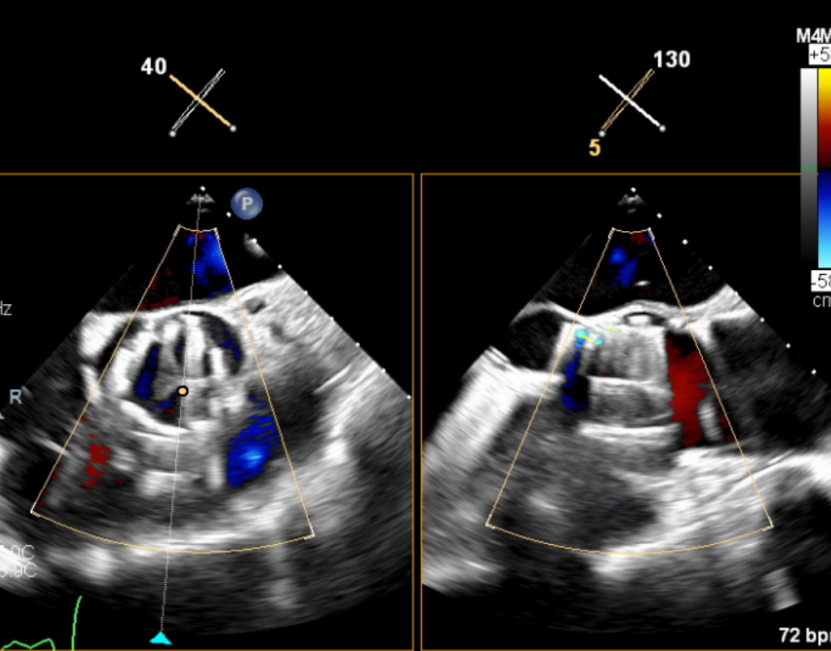

输送器顺利跨瓣,释放外鞘管,开始定位释放,超声评估可见定位件入窦可,后释放内鞘管,打开瓣架,瓣叶活动良好,无瓣周反流,综合考虑瓣膜稳定良好,脱钩释放。

脱钩后输送器回收,瓣膜无位移及形变,确认瓣膜完全脱钩,回撤输送系统,超声再次评估,瓣膜位置及形态良好,无瓣周漏,峰值流速1.18m/s,平均压3mmHg,患者未诉不适,入路缝合后返回病房。